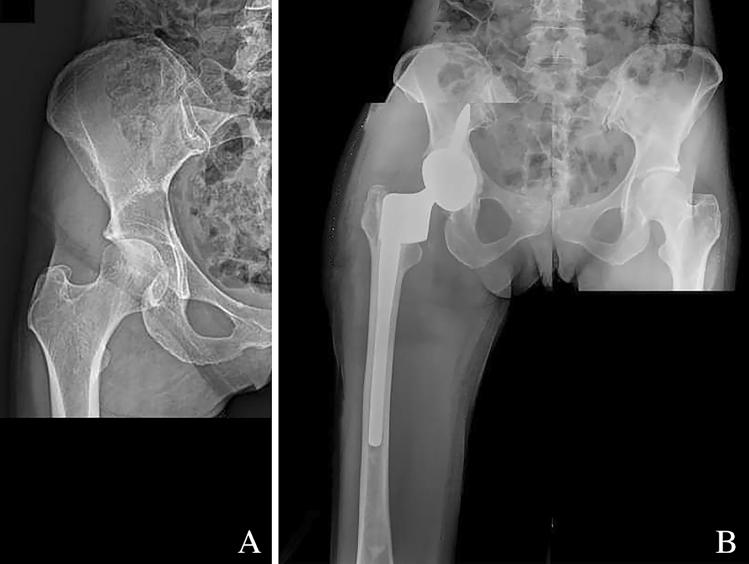

Stemmed acetabular cups are suitable for reconstruction in case of important bone loss. Nevertheless, their use is not so common, because generally judged very invasive and technically difficult to implant. The aim of the present review is to verify the results of their use and to evaluate indications and complications.

13 studies were selected, for a population of 424 patients and 428 hips. The main indication was reconstruction after tumor removal; the primary non-oncologic indication was revision for aseptic loosening. The most frequent complications were aseptic loosening and implant failure (16.2%), followed by deep infection (11.3%) and dislocation (9.8%). The average MSTS score was 65.9%; while data regarding functional results for degenerative cases are quite fragmented. The 5-years implant survival was 73.6%.

带柄髋臼杯适用于严重骨量丢失的重建。然而,它们的使用并不常见,因为一般认为它们具有很强的侵袭性,且植入技术难度较大。本综述旨在验证其使用效果,并评估其适应证和并发症。

共选择了 13 项研究,涉及 424 例患者和 428 髋。主要适应证为肿瘤切除后重建;主要非肿瘤性适应证为无菌性松动翻修。最常见的并发症是无菌性松动和植入物失败(16.2%),其次是深部感染(11.3%)和脱位(9.8%)。平均 MSTS 评分为 65.9%;而关于退行性疾病功能结果的数据则相当分散。5 年植入物存活率为 73.6%。